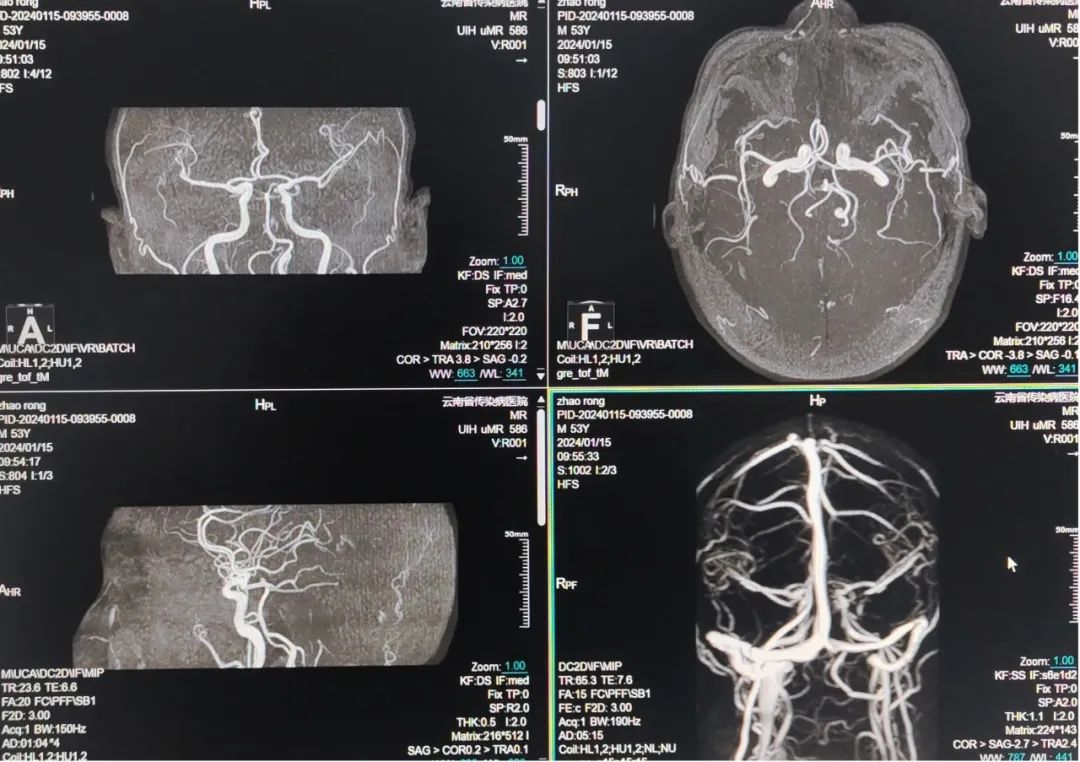

联影uMR586全数字超导磁共振成像系统搭载联影最新一代光梭成像技术,是目前国内外最先进的1.5T以下磁共振成像设备:在硬件方面,配置业内最先进的光梭成像平台,具有优异的磁场均匀性、高效的全数字化射频系统及一体化高密度相控阵线圈设计等顶级的硬件配置;在软件方面,量身定制如自由呼吸、GRE、ARMS等运动伪影抑制技术,体部磁敏感技术等多种高级应用软件,在为患者带来更高舒适度的同时,有效提高扫描速度、显著提高图像质量、提高检查成功率和微小病灶检出率。

uMR 586光梭磁共振成像系统具备极高分辨力,能够清晰显示颅脑、脊柱、腹部、血管、软骨韧带等部位,对软组织损伤、骨关节损伤、椎间盘突出、脊髓疾病等诊断优于X线及CT扫描,检查更为精准且无辐射,为早期发现、早期诊断、早期治疗疾病提供有力的技术保障。